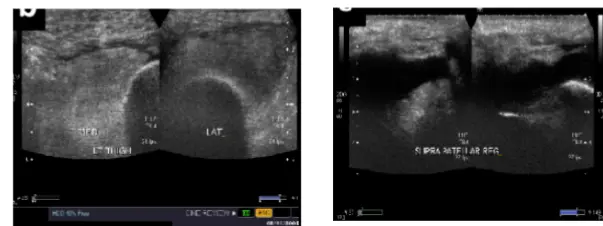

Knee Aspiration

| Effusion: Milking OR Patellar Tap | Detect presence and severity of joint fluid | Large Effusion visible: Patellar Tap (Balloting): ![]() | Minimal effusion: Fluid demonstrable with “milking.” Mild effusion: Fluid pushed away, then reappears. Moderate effusion: Fluid not pushed away. Moderate/severe effusion: Positive patellar tap (balloting). | |